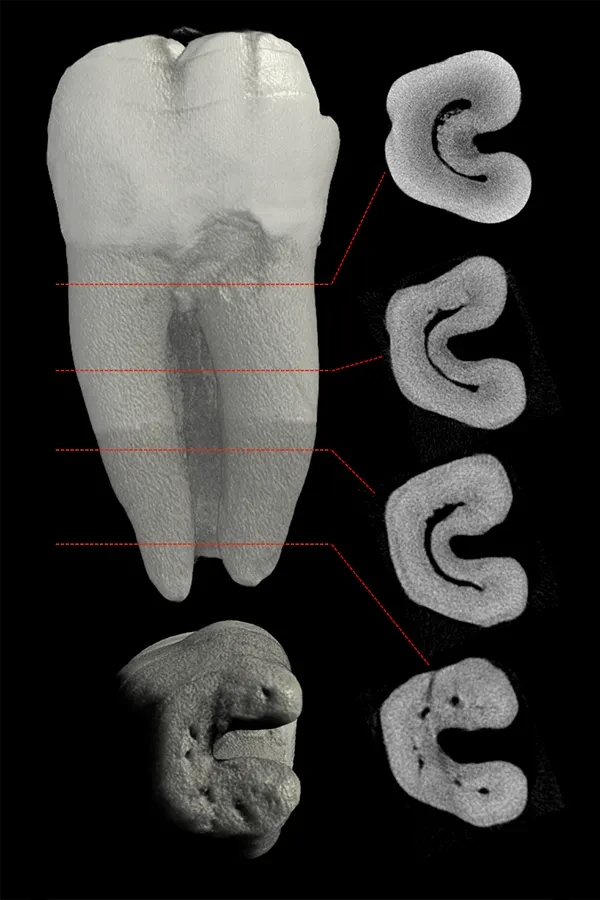

Wurzelkanalanatomie eines

zweiten Unterkiefermolaren

Bildquelle: Dr. Marco Versiani - www.rootcanalanatomy.com